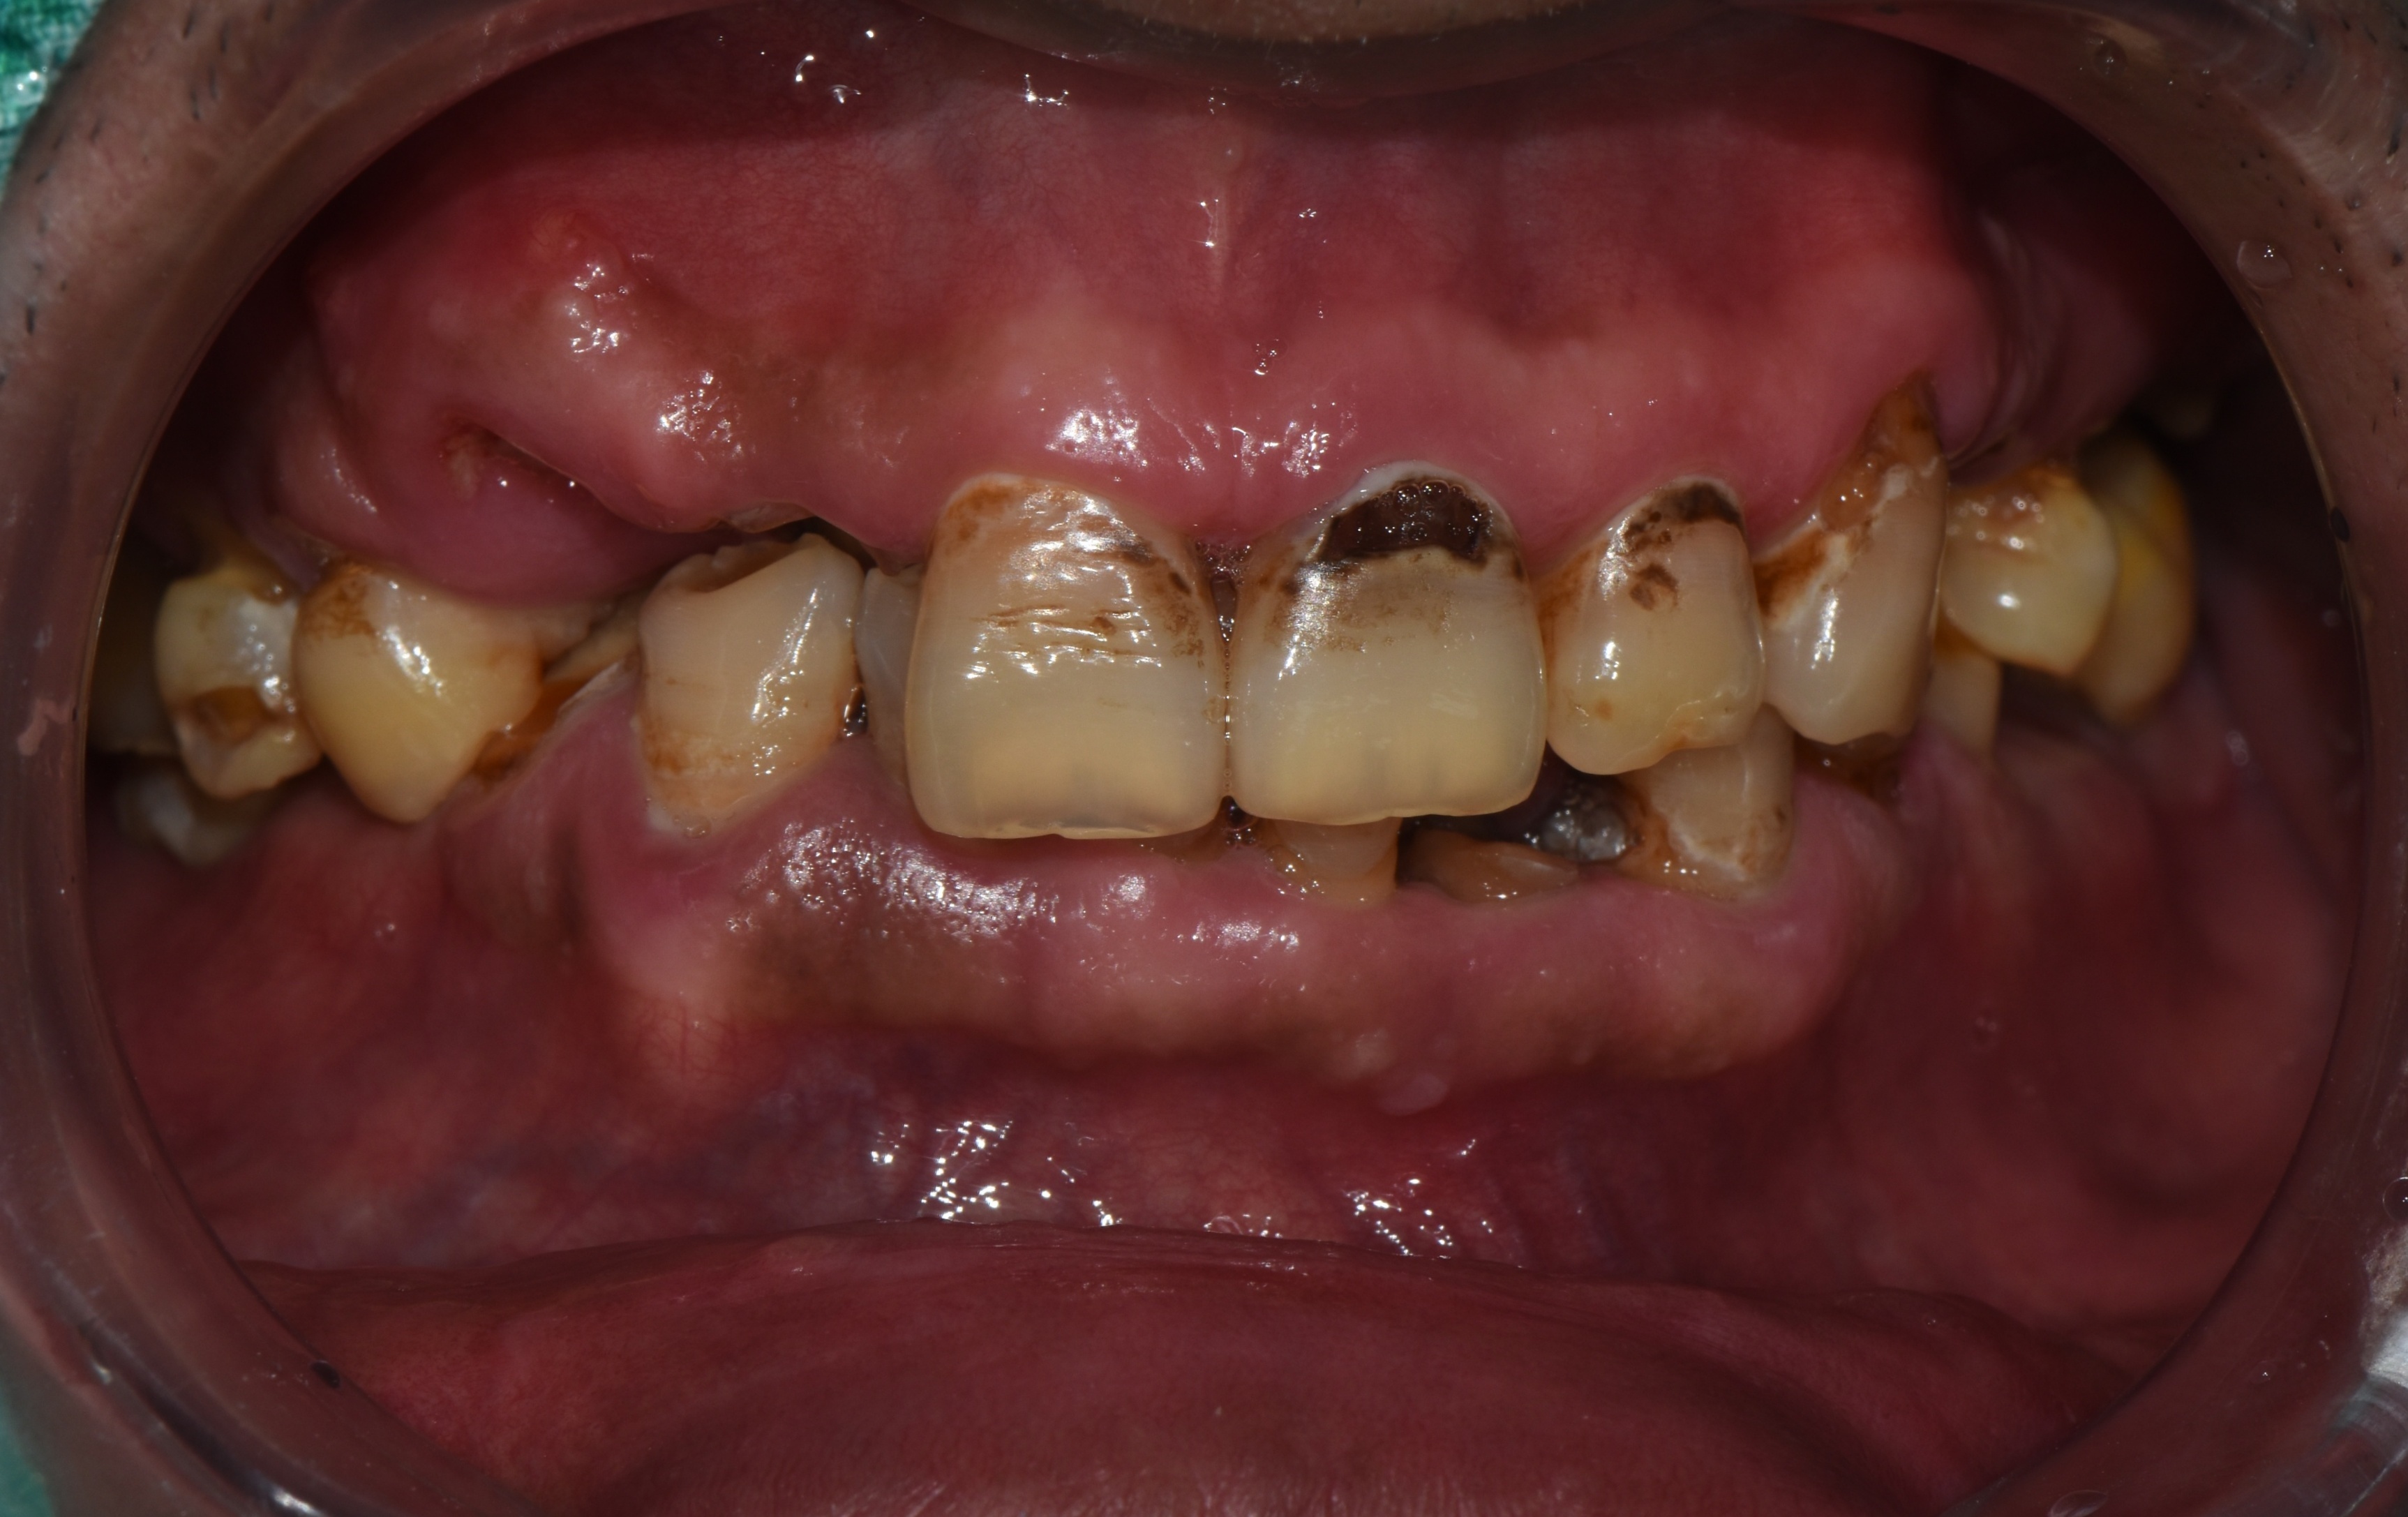

다수 치아의 우식으로 전체 임플란트를 진행한 치료 증례 2026-02-20 hit.248 |

촬영일시: 2025.05.27